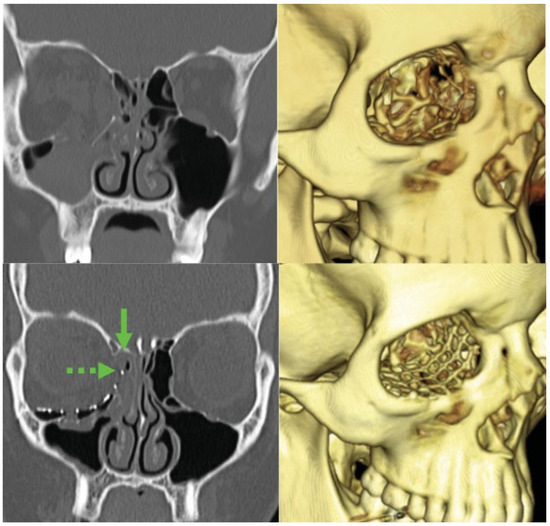

Standard protocol dictated postoperative evaluation for a minimum of 3 months. However, due to the nature of the patient population, numerous patients were lost to followup before this time point. The mean follow-up for patients with isolated medial wall fractures was 2.6 weeks (range, 2–3 weeks) and that for combined medial wall and floor fractures was 9.5 weeks (range, 2–34 weeks). Postoperative CT scans were obtained for three of the medial wall fracture patients and for eight medial wall and floor fracture patients. Although the MEDPOR implants are difficult to visualize on CT scan (►Figure 3), the orbital contents were seen to be reduced in a satisfactory position in all the three patients with isolated medial wall fractures. The MEDPOR TITAN implants were seen to be in a good position in seven patients. In one patient, the implant slid off the medial fracture ledge with the edge of the implant resting in the ethmoid sinus (►Figure 6). Despite this, the patient had no visual complaints and did not require reoperation. The combined transcaruncular and transconjunctival approaches were incorporated into a diverse range of periorbital procedures and allowed for precise and stable placement of the implant (►Figs. 3–6).

Figure 6. A 24-year-old woman with a large right-side combined orbital floor and medial orbital wall blowout fracture from a traumatic fall. The fracture area was 7.5 cm2 and was covered with MEDPOR TITAN. Preoperative scan and 3D rendering (top), postoperative scan and 3D rendering (bottom). Note that the superior edge of the implant (dotted arrow) slid off the fracture line (solid arrow).